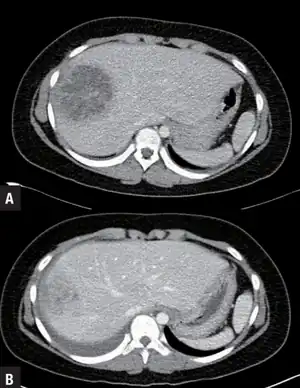

a)Day 1 showing pyogenic liver abscess b)hospital day 21 showing improved pyogenic liver abscess, after intravenous antibiotic